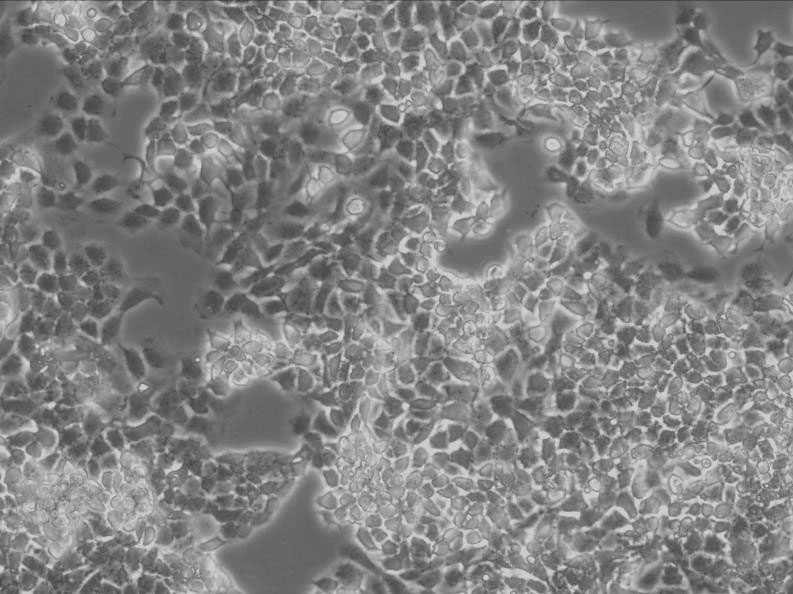

BeWo细胞:人胎盘绒膜癌细胞系

细胞背景资料:取自人绒癌脑转移组织,在仓鼠颊囊移植传代8年。利用移植瘤组织进行体外培养,建立细胞系。利用不同传代方法建立了不同亚系,JEG-3是其衍生克隆。该细胞可以产生雌激素、孕激素、雌酮、雌二醇、雌三醇、hCG、胎盘催乳素、角蛋白。

细胞形态:上皮细胞样

细胞生长:贴壁

细胞传代方法:1:3传代,3-4天换液一次